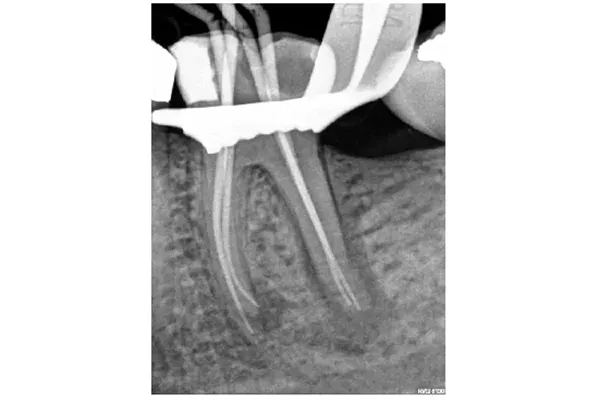

Máy định vị chóp điện tử hoạt động bằng cách sử dụng cơ thể để hoàn thành một mạch điện. Một bên của máy được kết nối với niêm mạc miệng và bên kia với dũa. Mạch được hoàn thành khi dũa tiếp xúc với mô nha chu tại CDJ.

8. Quy trình sử dụng máy định vị chóp điện tử

Tôi giữ máy định vị chóp kết nối và sử dụng nó trong suốt quá trình làm sạch và tạo hình.